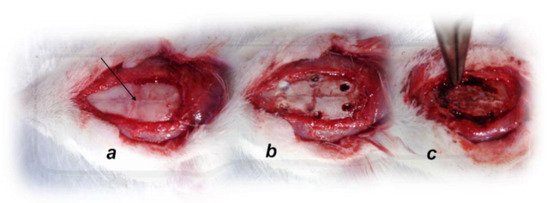

Recording of brain swelling was performed in rats at 15 min after the complete calvariectomy, and recording with a camera attached to a VMS-004 Discovery Deluxe USB microscope (Veho, Denver, CO, USA) was performed. Briefly, six burr holes were drilled in three horizontal lines, with all of them medial to the superior temporal lines and temporalis muscle attachments. The rostral two burr holes were placed just basal from the posterior interocular line, the basal two burr holes were placed just rostral to the lambdoid suture (and transverse sinuses) on both sides, respectively, and the middle two burr holes were placed in the line between the basal and rostral burr holes (Figure 1).

Figure 1. Animal preparation for the assessment procedure. (a). For superior sagittal sinus pressure recording, a single burr hole was placed in the rostral part of the sagittal suture, above the superior sagittal sinus (arrow); (b). Six burr holes drilled in three horizontal lines, with all of them medial to the superior temporal lines and temporalis muscle attachments; (c). Complete calvariectomy.